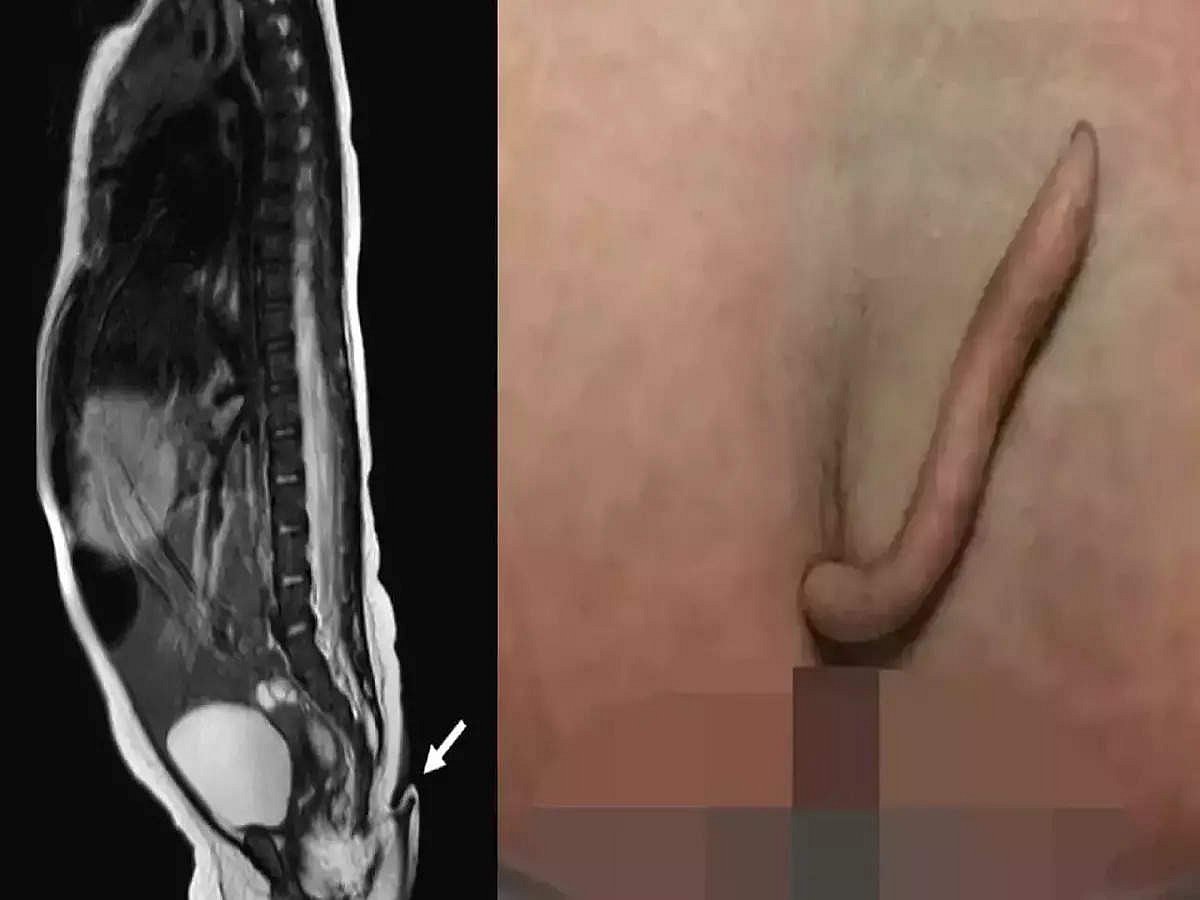

இந்த நிகழ்வு குறித்து அந்த மருத்துவமனை அதிகாரிகள் கூறுகையில், "நிறைமாதத்தில் அறுவை சிகிச்சை மூலம் பெண் குழந்தை பிறந்தது. அந்த குழந்தைக்கு, 5.7 செ.மீ நீளத்தில் (2 அங்குலம்) மென்மையாகவும், கூர்மையாகவும் வால் ஒன்று காணப்பட்டது. தோலால் மூடப்பட்ட நிலையில் இருந்த அந்த வாலில் மெல்லிய ரோமங்களும் இருந்தன. அந்த வால், கூர்மையான முனையை நோக்கி குறுகிக் காணப்பட்டது.

மெக்சிக்கோவில் இப்படி ஒரு குழந்தை பிறப்பது இதுதான் முதல் முறை. அந்த வாலை தொட்டு அசைக்கும்போது குழந்தை எந்த வலியையும் உணரவில்லை. ஆனால் ஊசியால் குத்தியபோது குழந்தை வலியை உணர்ந்து கத்தியது.

குழந்தைக்கு தற்போது அறுவை சிகிச்சை செய்யப்பட்டு அந்த வால் அகற்றப்பட்டது. மேலும் அதை ஆய்வுக்கு அனுப்பினோம். தசை மற்றும் நரம்புகளைக் கொண்ட உண்மையான வால் என்பது கண்டறியப்பட்டுள்ளது. இது விலங்குகளுக்கு இருப்பது போன்று எலும்புகளற்றது என்பது தெரியவந்தது" என்றார்.